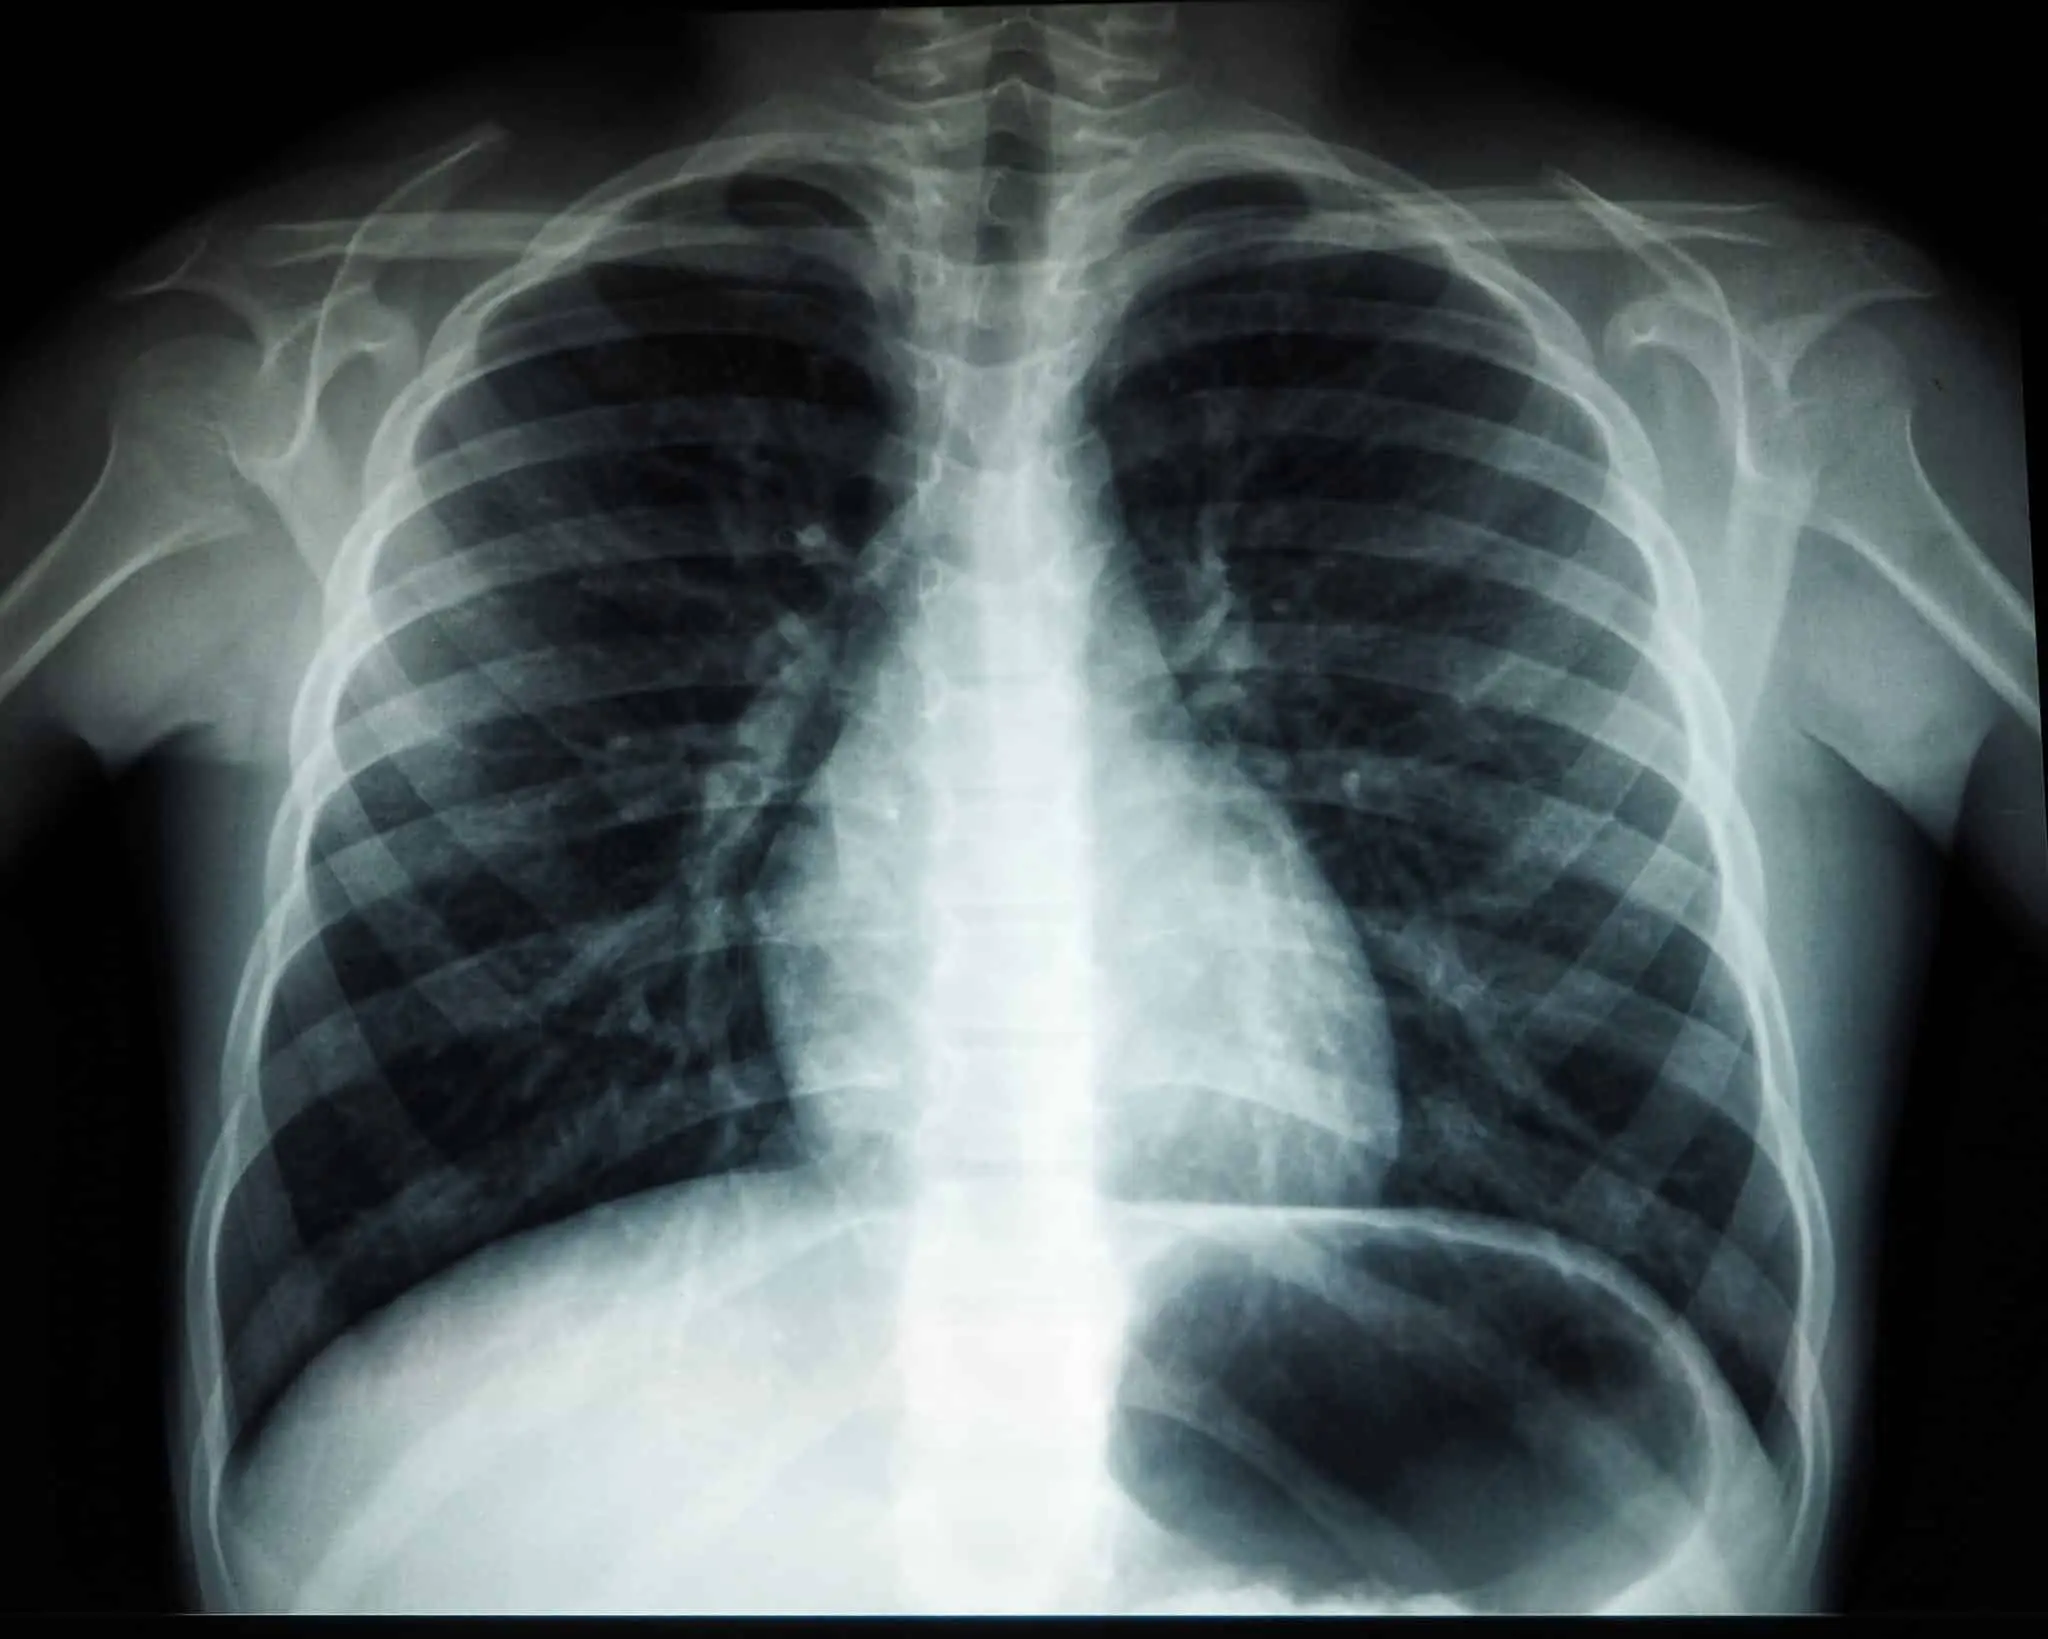

Фото: naked-science.ru